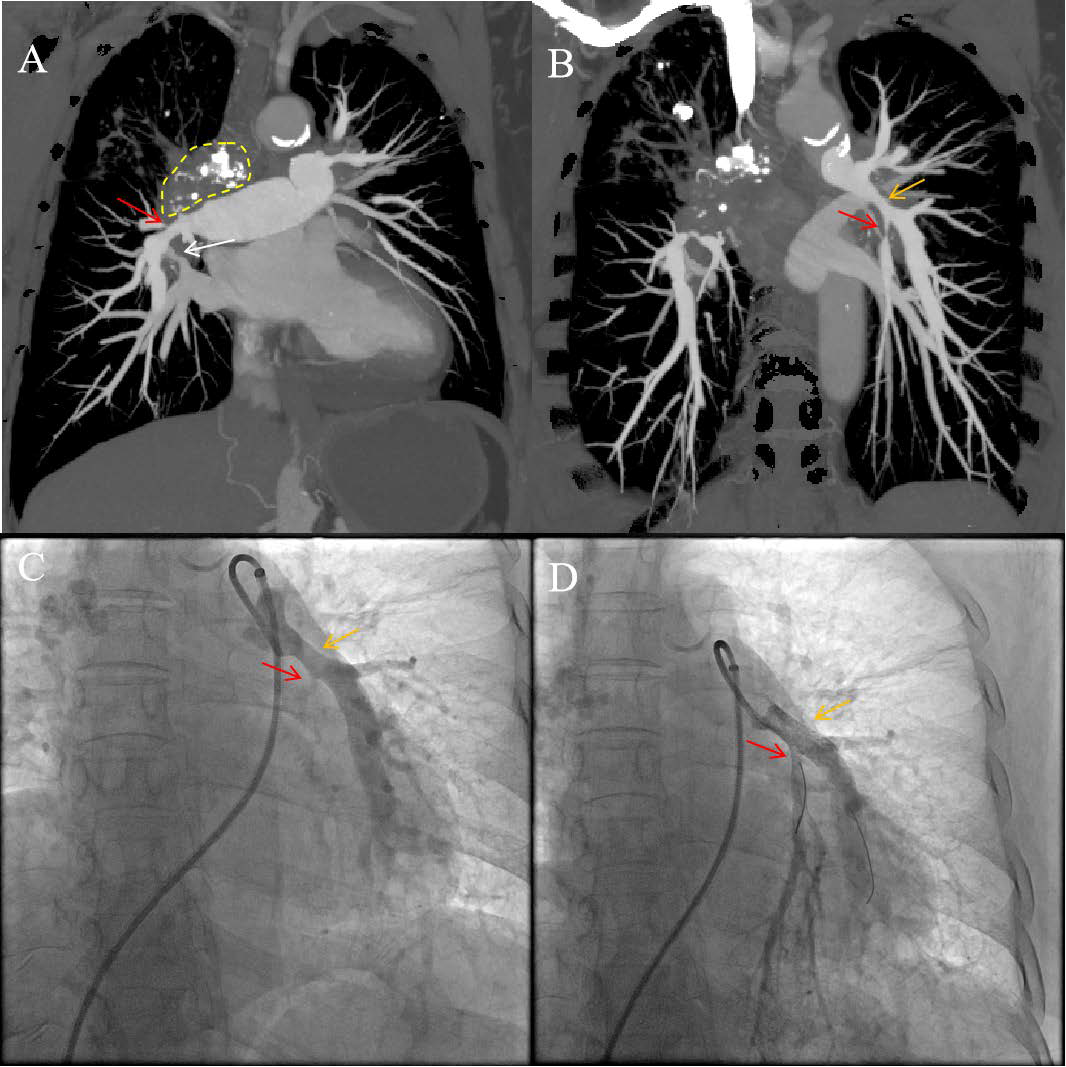

The Role of CT-Guided Optimal Fluoroscopic Projection Angle to Guide Stenting of Occluded Pulmonary Arteries

Yao Mi, MD, Mingwang Ding, MD, Yunshan Cao, MD, PhD

1-4